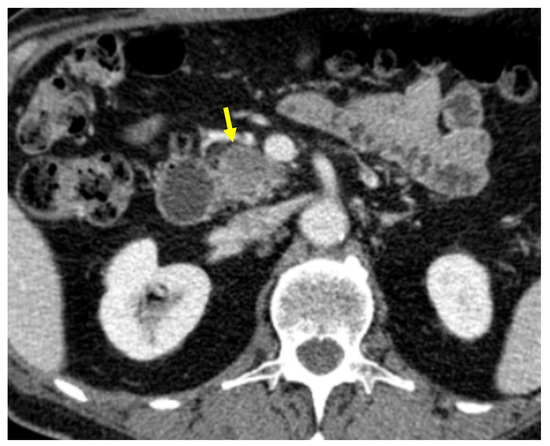

Tumor margins showed a significant difference in the two groups, appearing well-defined in only 6 (6.98%) metastatic patients and ill-defined in the remaining 80 (93.02%); in the non-metastatic group, the margins appeared well-defined in 132 (65.35%) and ill-defined in 70 (34.65%) tumors (Figure 2, Figure 3, Figure 4 and Figure 5).

Figure 4. Pancreatic lesion with ill-defined margins (arrow) on CT examination in pancreatic contrast phase.